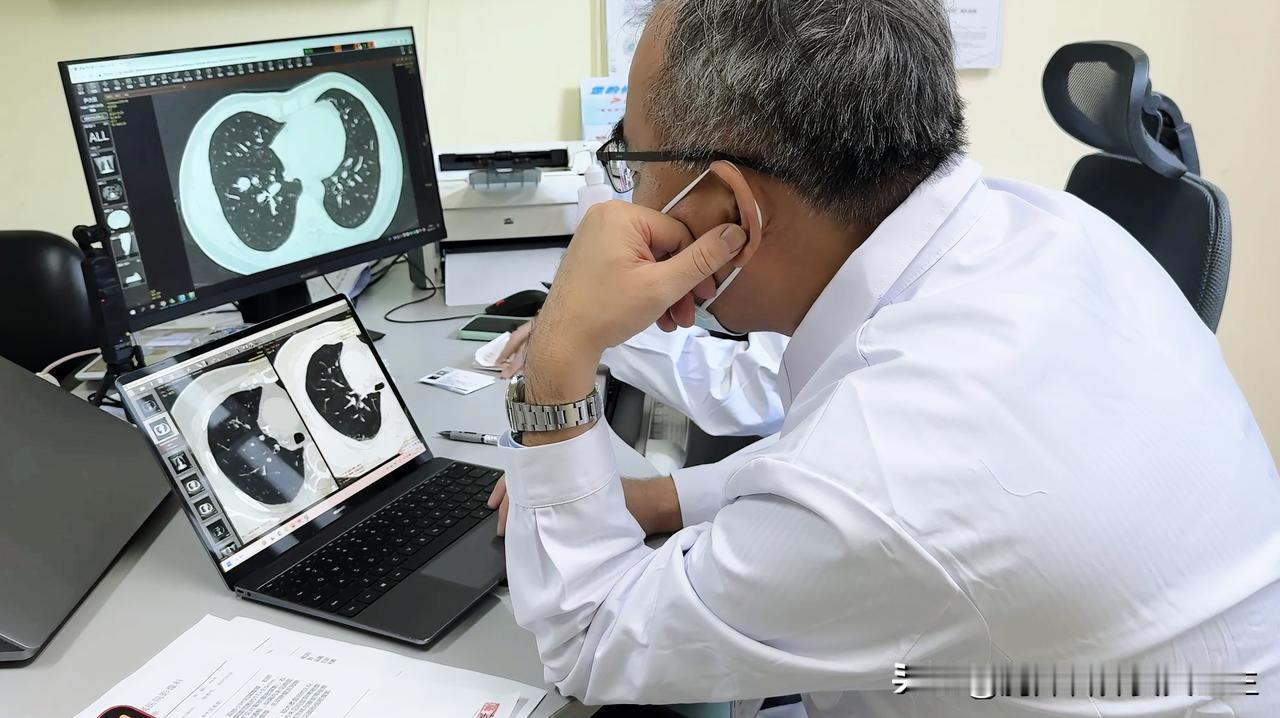

检查与诊断

- 体格检查:医生通过间接鼻咽镜或纤维鼻咽镜检查,可直接观察腺样体的大小和形态。

- 影像学检查:如鼻咽部X线侧位片、CT等,能清晰显示腺样体的大小及与周围组织的关系,有助于评估病情严重程度。